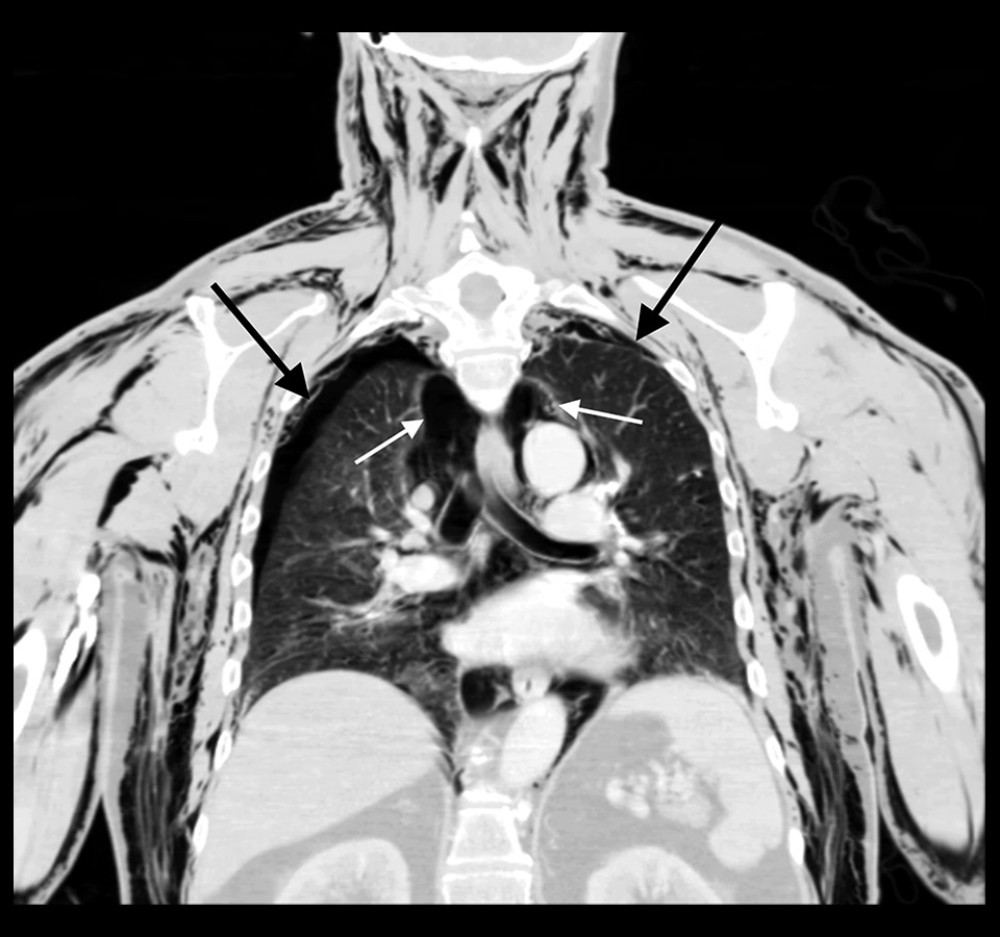

In the emergency department, he was afebrile (37°C), with a heart rate of 80 beats per minute, blood pressure 104/70 mmHg, respiratory rate of 36 breaths per minute with SpO2 of 100% while breathing 2 L/min of oxygen via nasal cannula. He was alert and oriented in mild distress. A physical exam revealed a marked crepitus from head to thigh with bilateral orbital emphysema making it difficult to visualize his left pupil. He had a regular rate and rhythm on cardiac auscultation. Palpable crepitus was appreciated throughout the anterior chest, but without Hamman’s sign or an accessory crunching sound. Respirations were non-labored with decreased breath sounds bilaterally. His scrotum was tender to palpation with a dehis-cent left scrotal wound. The scrotum was not grossly swollen and had no signs of free air or rapid expansion. Routine laboratory results were unremarkable except for mild leukocytosis of 12.2 k/mm3 (Table 1). A chest X-ray disclosed bilateral pneumothoraces, pneumomediastinum, and excessive sub-cutaneous air. Two chest tubes were placed before obtaining computed tomography (CT) of the chest, abdomen, and pelvis. Being in a small local emergency department, he was transferred to a larger regional hospital for further treatment. Upon arrival, concern for worsening of the right-sided pneumothorax prompted a repeat CT chest, abdomen, and pelvis (Figures 1–3). This study revealed that the chest tube was not communicating with the pneumothorax, which had increased in size from the previous report. He had placement of an additional chest tube. On hospital day 3, with resolution of the pneumotho-races, his chest tubes were removed and he was discharged in stable condition.